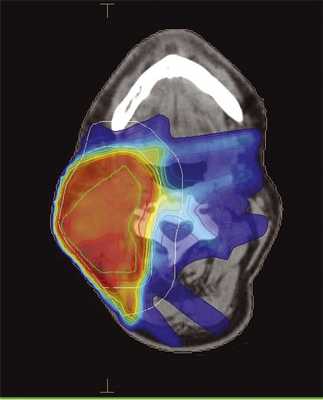

Больной С., 1951 года рождения, проходил лечение в клинике МРНЦ им. Цыба в январе 2010 г. с диагнозом: плоскоклеточный рак гортани cT2N2M0. Проведен радикальный курс одновременной химиолучевой терапии, в конвенциональном режиме РОД 2 Гр до СОД 60 Гр. После окончания лечения выявлена остаточная опухоль в лимфатических узлах шеи, однако больной категорически отказался от операции. В мае 2014 г. отметил бурный рост лимфатических узлов, но за помощью обратился только в декабре 2014 г. Проведен курс повторной конформной лучевой терапии в режиме гипофракционирования РОД 3 Гр до СОД 45 Гр (EQD2 =54 Гр), с одновременной химиотерапией (цисплатин). Больному предварительно была проведена реконструкция ранее полученных доз, не выявившая превышения значений толерантности (табл. 3). При этом была выбрана методика IMRT, поскольку это позволяло в значительной степени снизить нагрузку на ранее облученную гортань (рис. 3).

Рис. 3. Дозное распределение при повторном облучении очага в носоглотке методикой IMRT. Градиентом цвета обозначен переход от максимальной дозы (красное) к минимальной (синий цвет, 10% от максимальной). Покрытие мишени (PTV) не менее 95%.